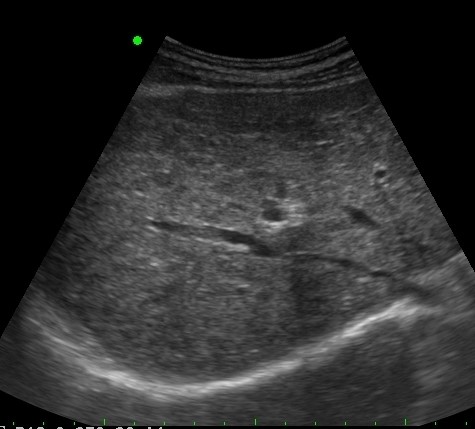

LIVER ) LC |

2019.05.11 мЎ°нҡҢмҲҳ: 219 |